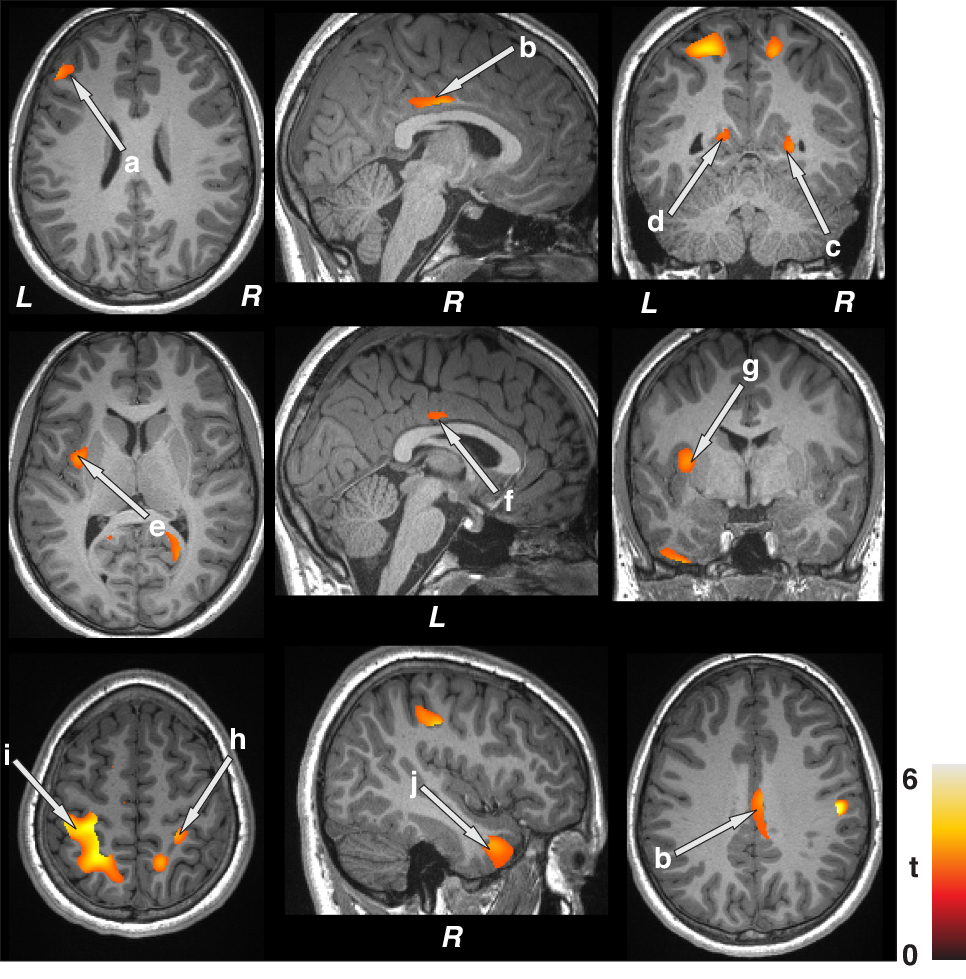

Fig. 3: Associations observed between gray matter volumes and focal seizure frequency indices using whole-brain voxel-by-voxel partial correlation procedures (covariates; age, sex, and BMI).

Positive correlations emerged between gray matter volumes and focal seizure frequency indices in children with epilepsy in the frontal cortices (a), bilateral mid (b, f) and posterior (c, d) cingulate, left insula (e), putamen (g), bilateral parietal cortices (h, i), and temporal cortices (j). Figure conventions are the same as in Fig. 1.